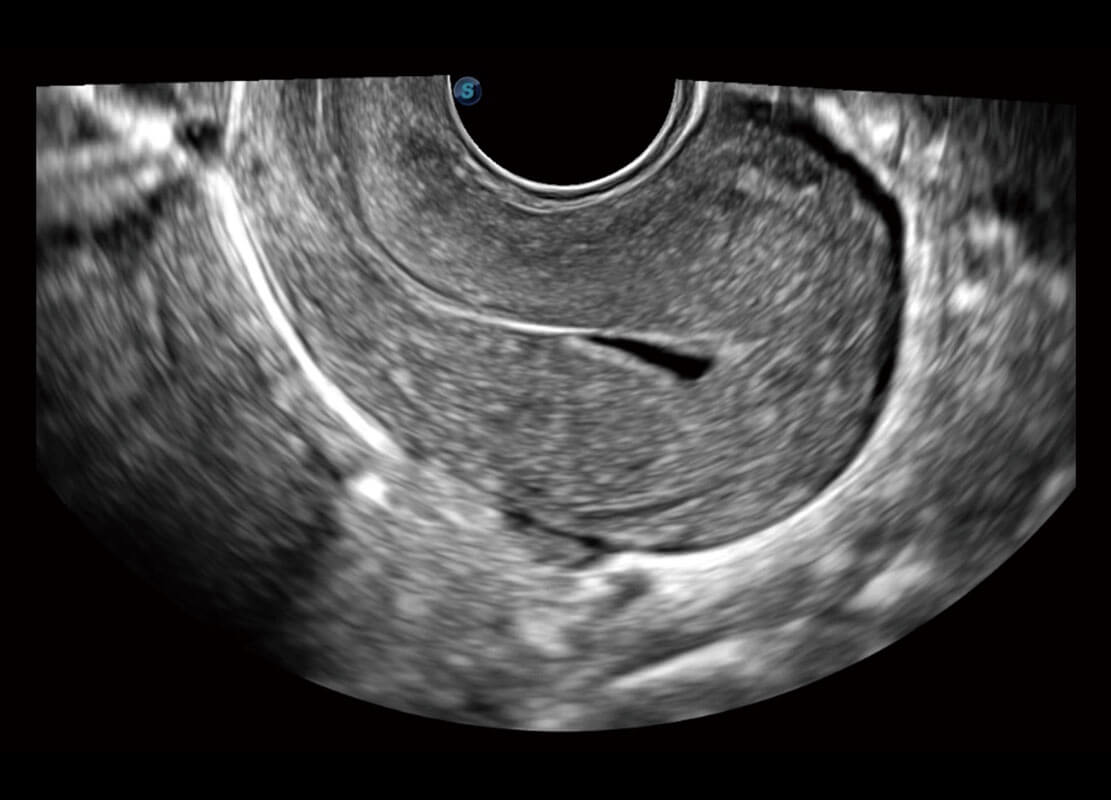

腔内三维-宫内节育器

腔内三维-光影成像